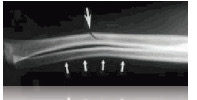

Stress fracture

Due to repetitive use. Also called hairline fracture. Appears like a crack on a x-ray